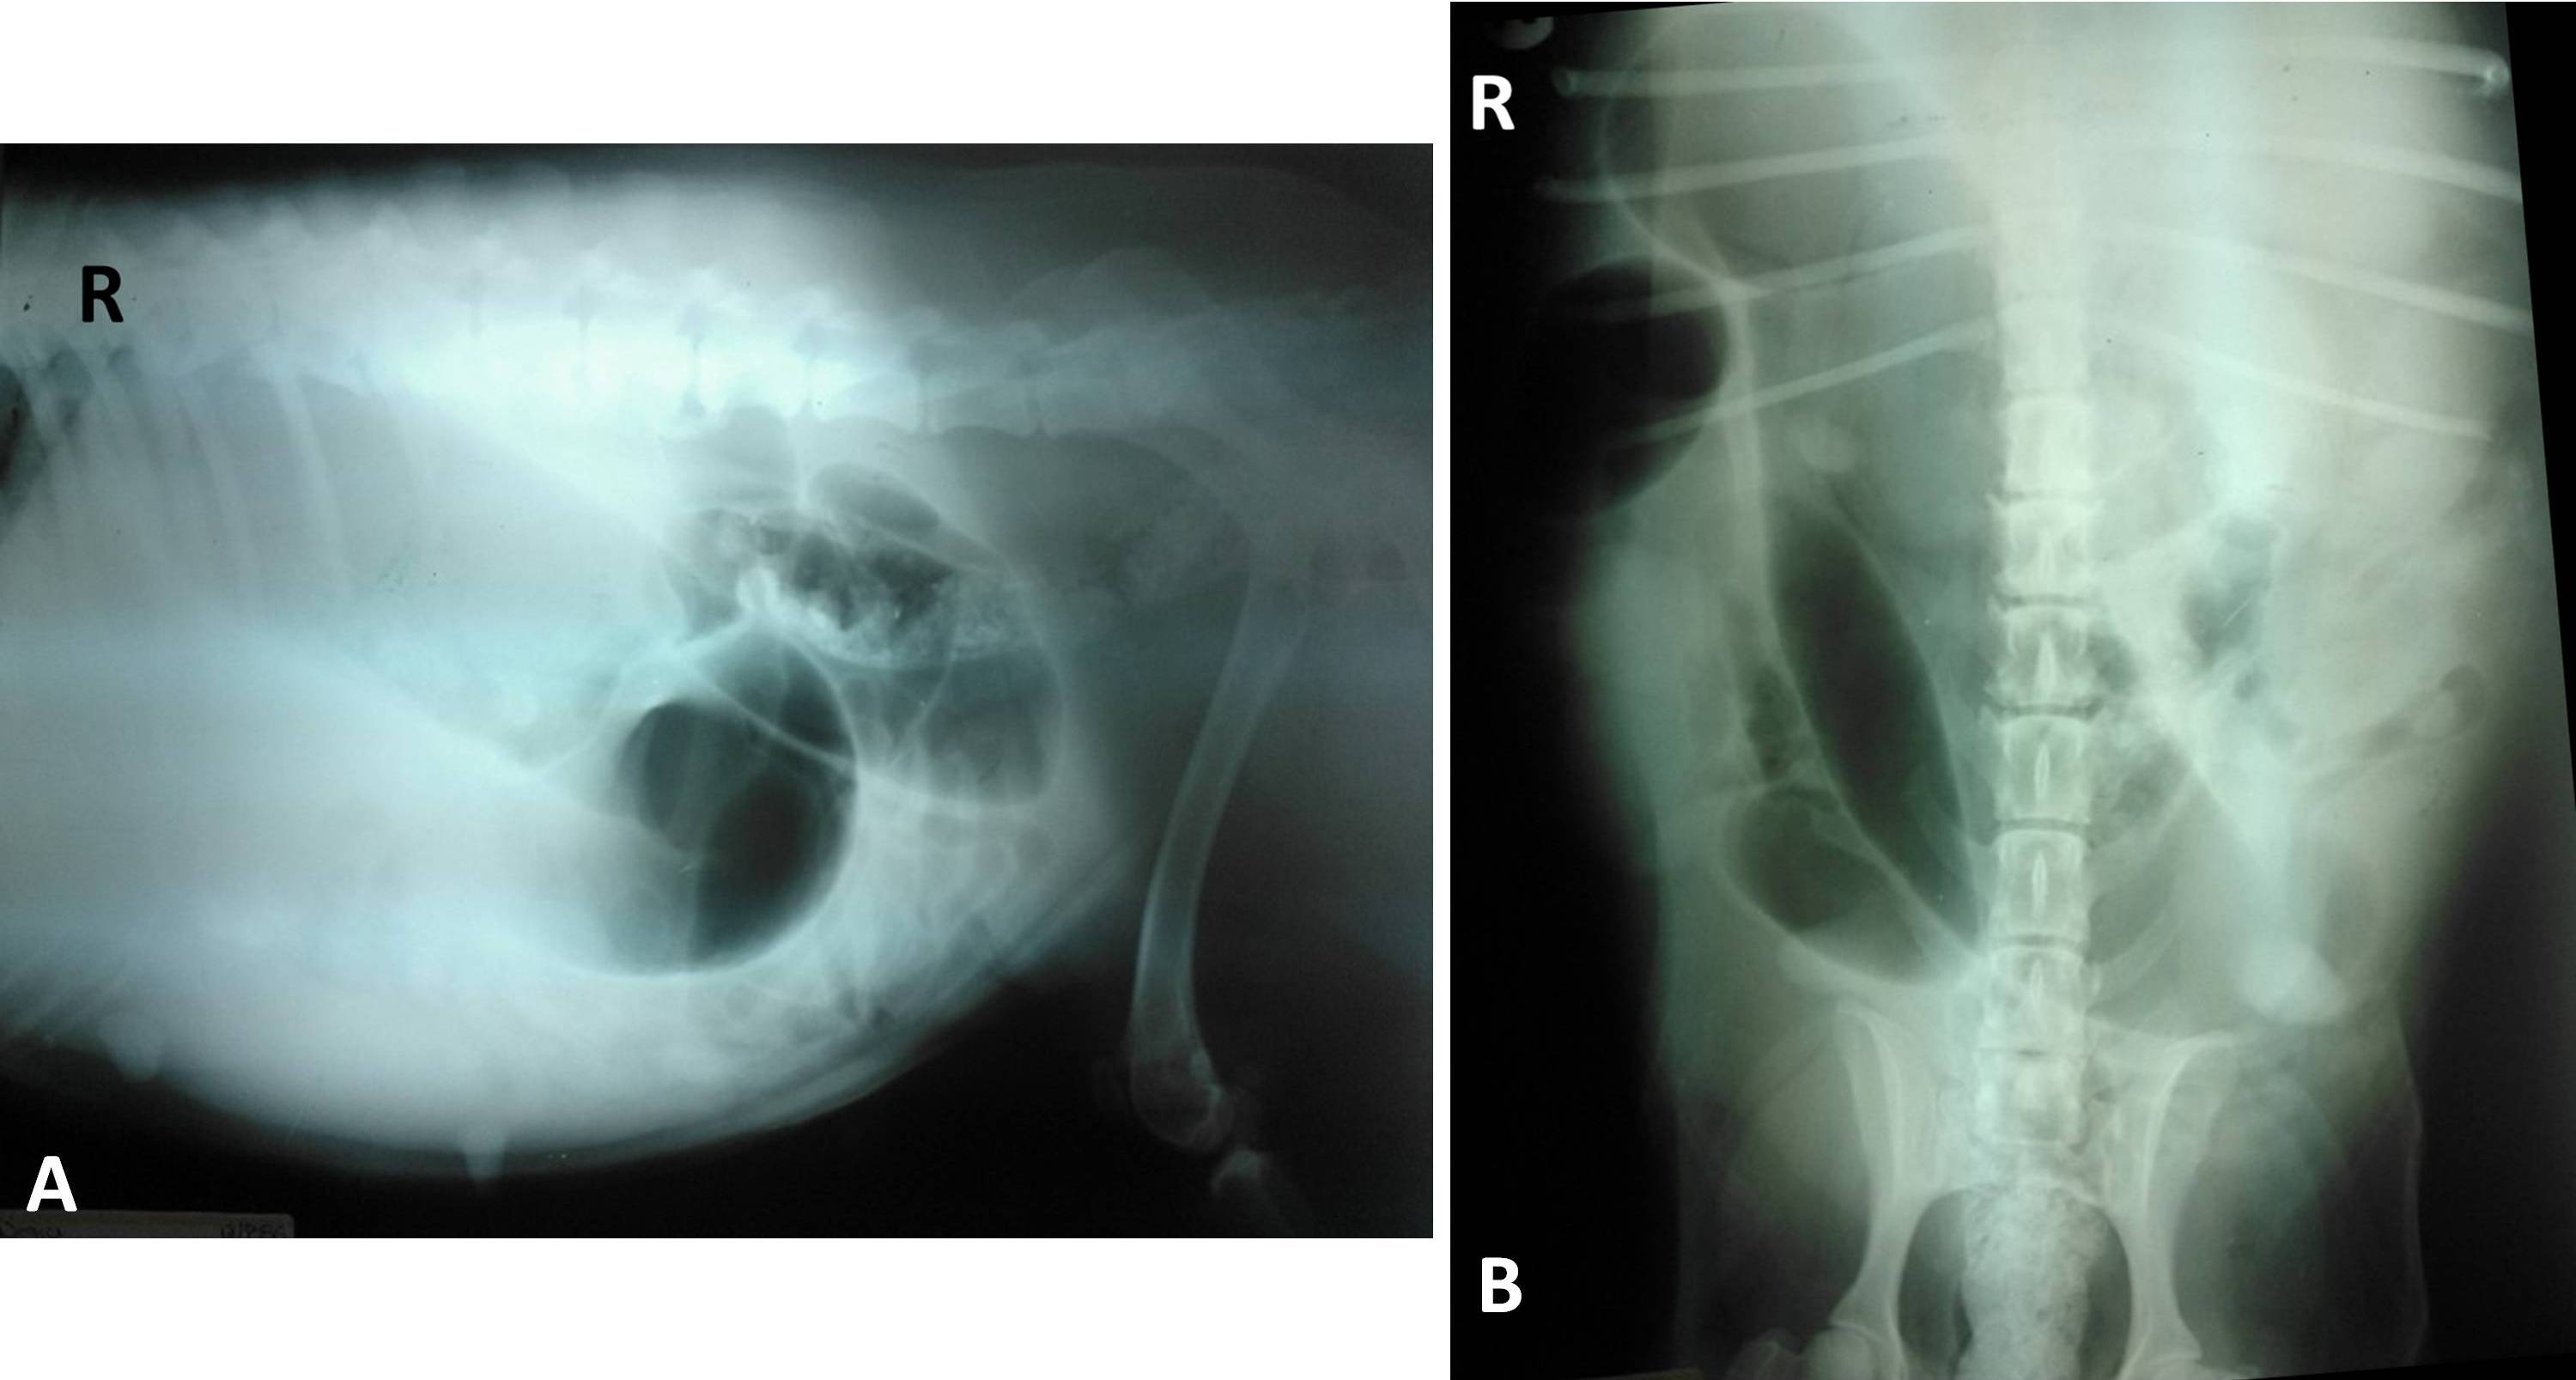

We report the case of a 9-year-old female Labrador retriever, presented to the Veterinary Teaching Hospital with a history of bloody/purulent and malodourous vulvar discharge, decreased appetite and progressive abdominal enlargement for about 20 days. Clinical examination showed a distended and painful abdomen and tympanic sounds on percussion. The patient also presented systemic inflammatory response syndrome (SIRS) and a leukemoid reaction with leukocyte count of 77.9 x 10 /L due to 62.32 x 10 /L lymphocytes. The abdominal radiography showed distended tubular structures occupying most of the abdomen; dorsal displacement of the colon in the left-right lateral projection was also found. The ultrasonographic study also revealed tubular structures in the mid-abdomen that contained flowing fluid presenting mixed echogenicity and hyperechoic particles in suspension. The exploratory celiotomy showed that the uterine horns were distended and contained a mixture of gas and liquid, hence an ovariohysterectomy was performed. The uterine fluid was collected with aseptic technique into a syringe and submitted to the clinical pathology laboratory for aerobic and anaerobic culture and antibiotic sensitivity. Hafnia alvei (now classified as Hafnia paralvei) was identified as the causative bacterial agent. Pyometra caused by gas-producing bacteria is a rare condition and is known as emphysematous pyometra. There are only six reports in the literature of this condition in bitches. A wide range of vaginal bacteria has been found in dogs with pyometra, but to our knowledge this is the first report of emphysematous pyometra caused by Hafnia paralvei in dogs.